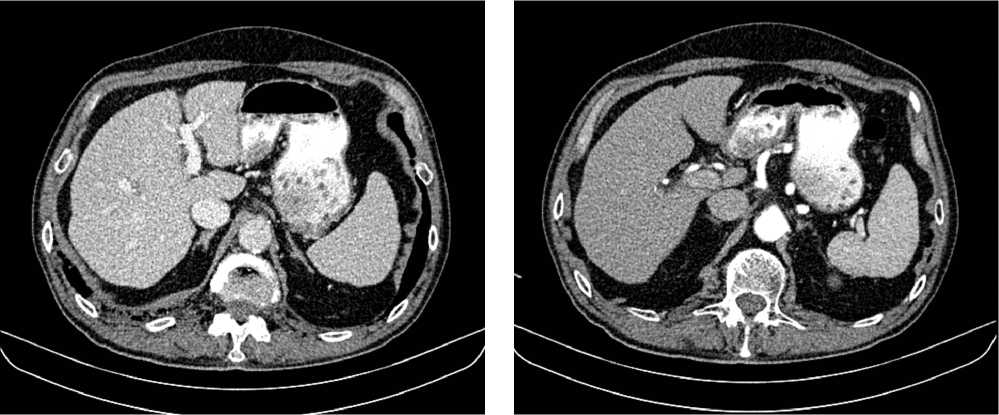

Выполнена компьютерная томография (КТ) органов грудной клетки, брюшной полости в июле 2019 г. Инфильтративных изменений в легких не обнаружено. Выявлено новообразование антрального отдела, малой кривизны и передней стенки желудка, распространяющееся на заднюю стенку, преимущественно на препилорический отдел. Имелись признаки локального перехода образования на большой сальник, гепатодуоденальную связку с периваскулярным ростом и признаками лимфоваскулярной инвазии. Многочисленные забрюшинные ЛУ сливались между собой в конгломераты размерами до 40 × 29 мм с частичным вовлечением почечных артерий. Также билобарно обнаружены немногочисленные очаговые образования в печени до 10 мм. Высказано подозрение на перитонеальный канцероматоз (рис. 3).

Рис. 3. Результаты компьютерной томографии органов брюшной полости у пациента 80 лет с диагнозом метастатический рак желудка с признаками микросателлитной нестабильности (июль 2019 г., до лечения)

Fig. 3. Results of a CT scan of the abdomen in an 80-year-old patient with metastatic MSI-H gastric cancer (July 2019, before treatment)

В результате обследования был установлен диагноз рака антрального отдела желудка (c)T4аN3вM1. По решению онкологического консилиума, учитывающего молекулярно-генетический профиль опухоли, а также возраст пациента, выраженность сопутствующей патологии (в анамнезе острое нарушение мозгового кровообращения (ОНМК), острый инфаркт миокарда (ОИМ), фибрилляция предсердий (ФП), постоянная форма), ограничивающей проведение ПХТ, была начата ИТ 1 линии пембролизумабом. С сентября 2019 г. по декабрь 2021 г. проведено 29 циклов ИТ 1 линии по схеме пембролизумаб в монорежиме с максимальным эффектом частичный регресс (рис. 4). Осложнений лечения не зарегистрировано.